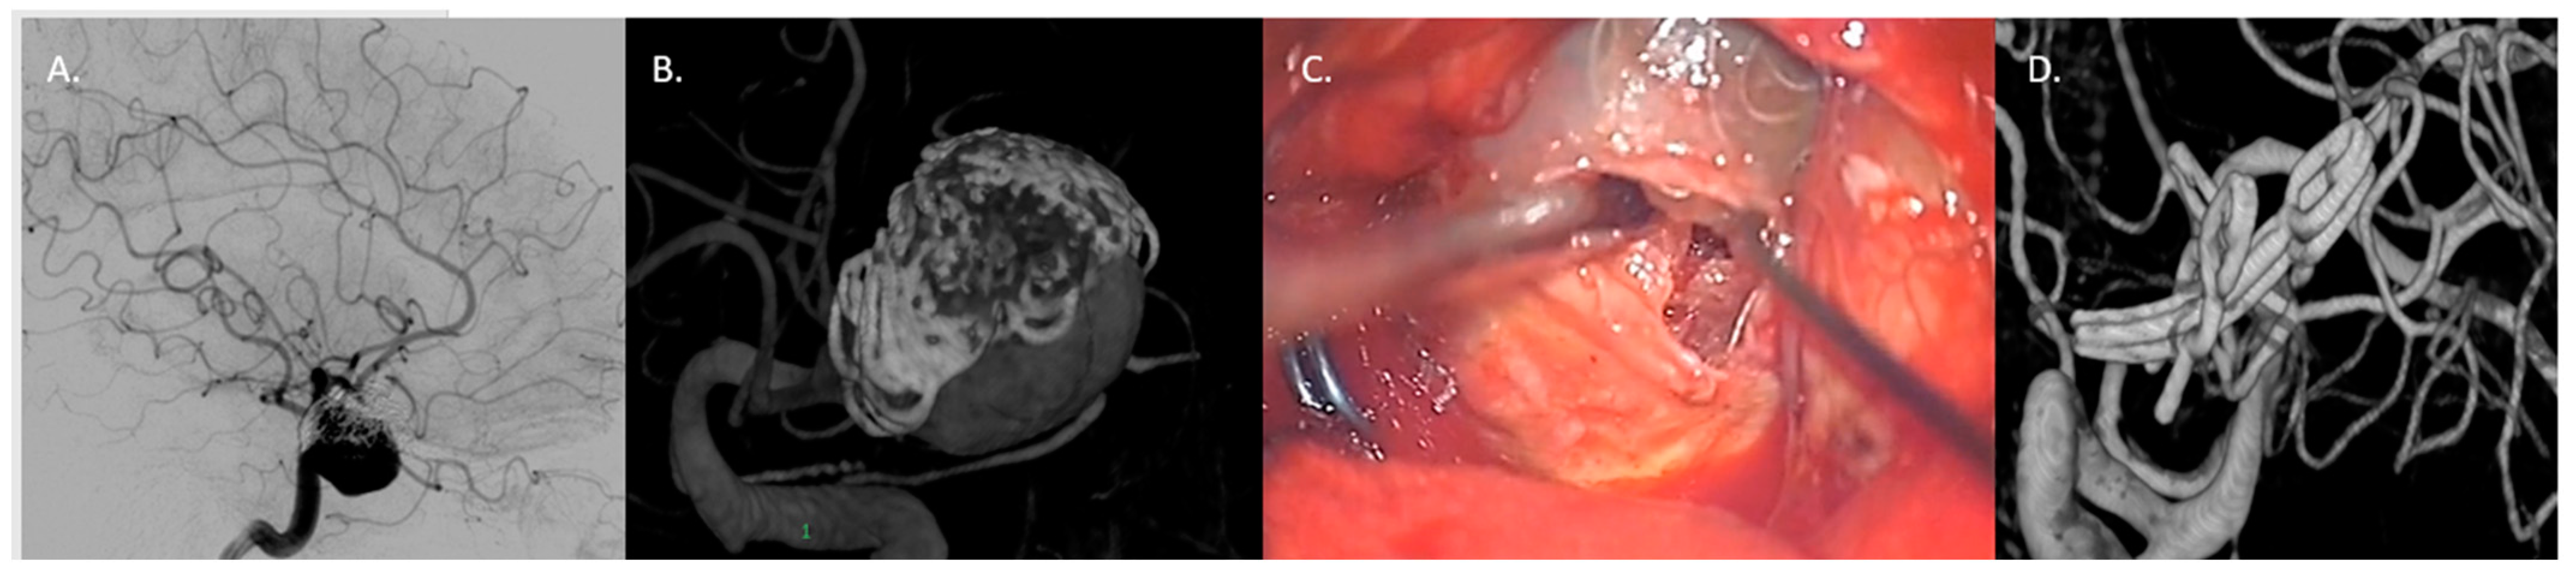

4.3.1. Large/Giant Aneurysm Size and Fusiform Shape